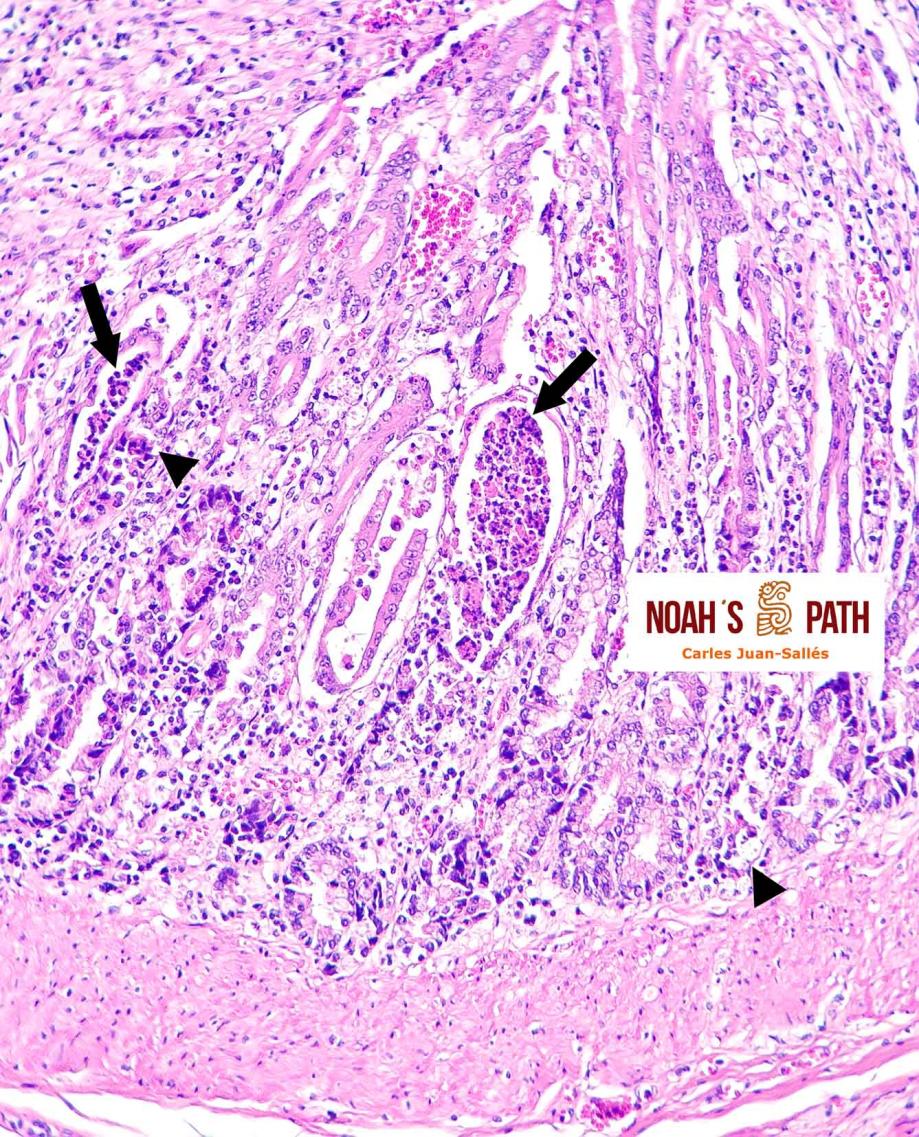

Estudio clínico-patológico e inmunohistoquímico de un brote de mortalidad en elands juveniles debido a infección intestinal por coronavirus en colaboración con Santiago Borragán del Parque de la Naturaleza de Cabárceno y Pepe Ramos de la University of Purdue.